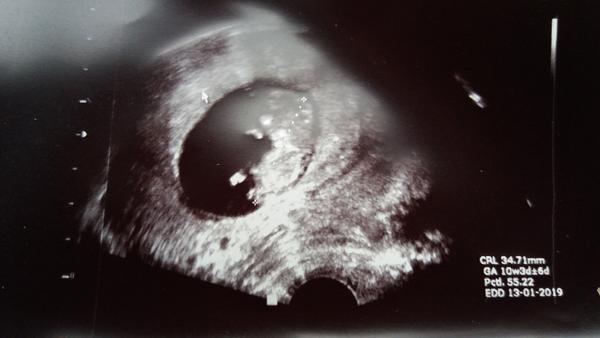

Já byla dnes ráno na další ko, mám 9+1, miminko v pořádku a už jsem viděla i jak se tam vrtí. To jsou tak zvláštní okamžiky... 2cm a už tančí😊

Jinak k té otázce na prvotrimestrální screening... u prvního těhotenství jsem na všechno koukala jak z jara, dr mi lupla prospekt na genetiku ať se tam objednám a bylo vymalováno. Až později jsem zjistila, že všechna vyšetření jsou nepovinná. Nicméně teď u druhého jdeme na screening taky, prostě chci vědět, že je miminko zdravé. Bohužel v blízké rodině se stalo, že se u mimi na tomto screeningu potvrdil Downův syndrom.